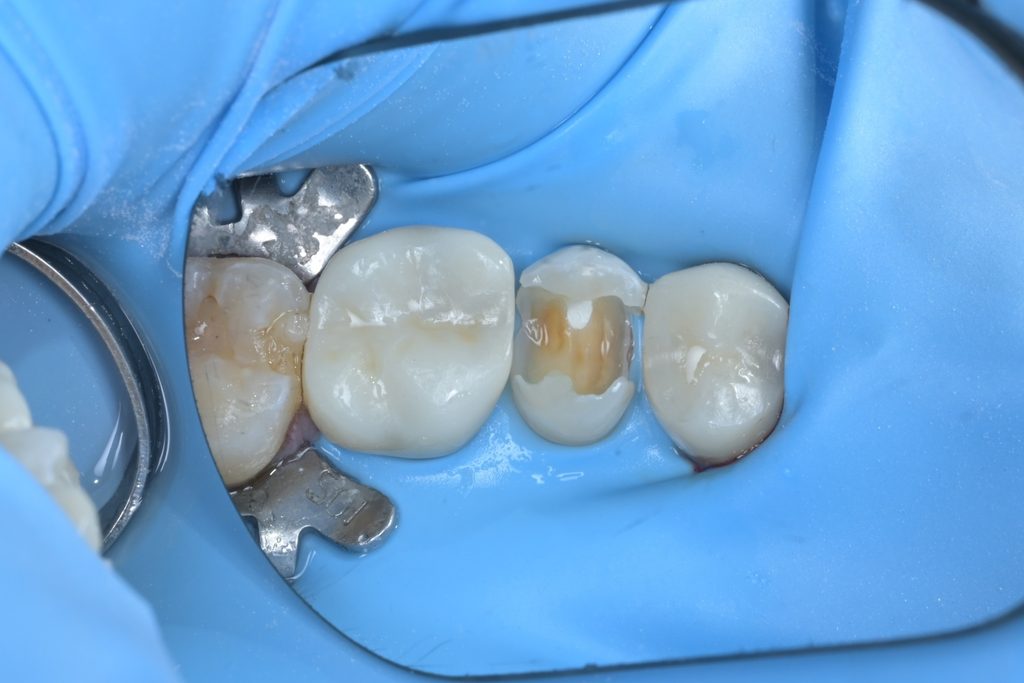

Step 5: 레진빌드업 수복

MTA가 경화되면, 그 위로 복합레진을 이용한 레진빌드업을 시행합니다. 인접면부터 교합면까지 층층이 적층하며 원래 치아의 해부학적 형태를 정밀하게 재현합니다.

치료 후 최종 마무리 및 결과

레진빌드업 완료 후, 교합지를 이용하여 반대편 치아와의 교합 접촉을 세밀하게 조정하고, 다이아몬드 버와 폴리싱 시스템을 사용하여 최종 연마를 진행했습니다.